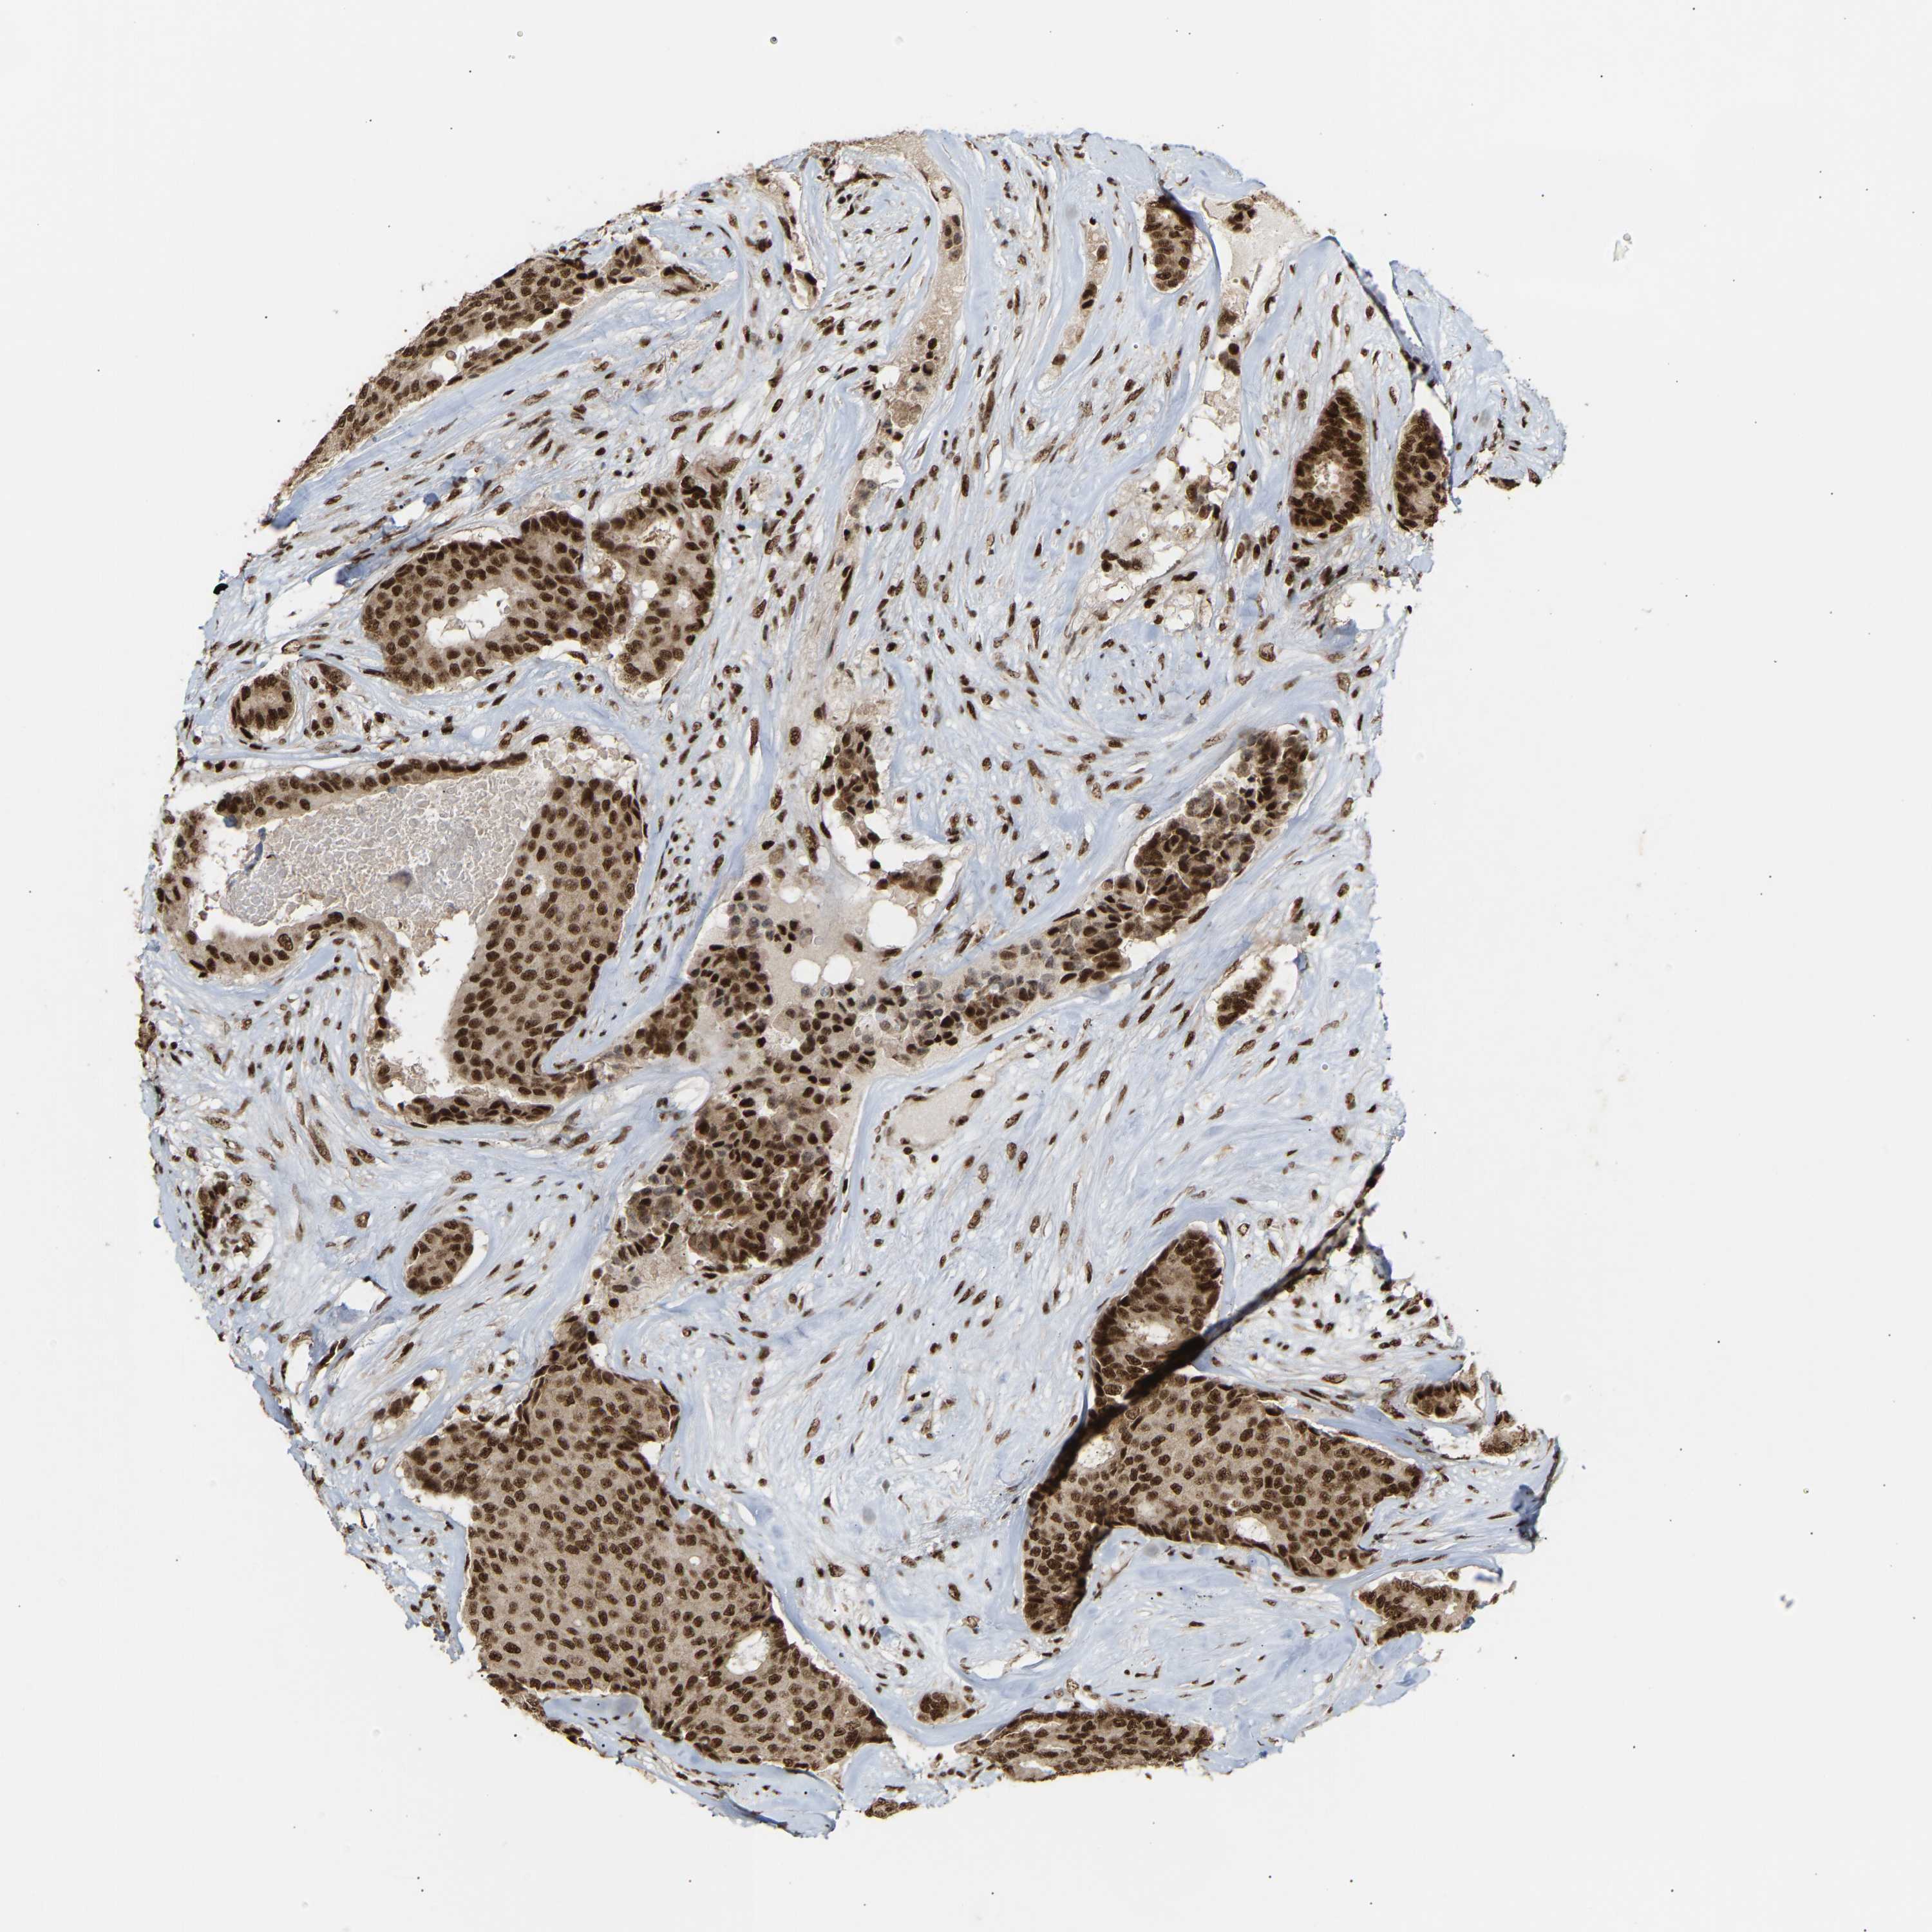

CANCER BREAST CANCER Show tissue menu

Breast cancer

Human cancer